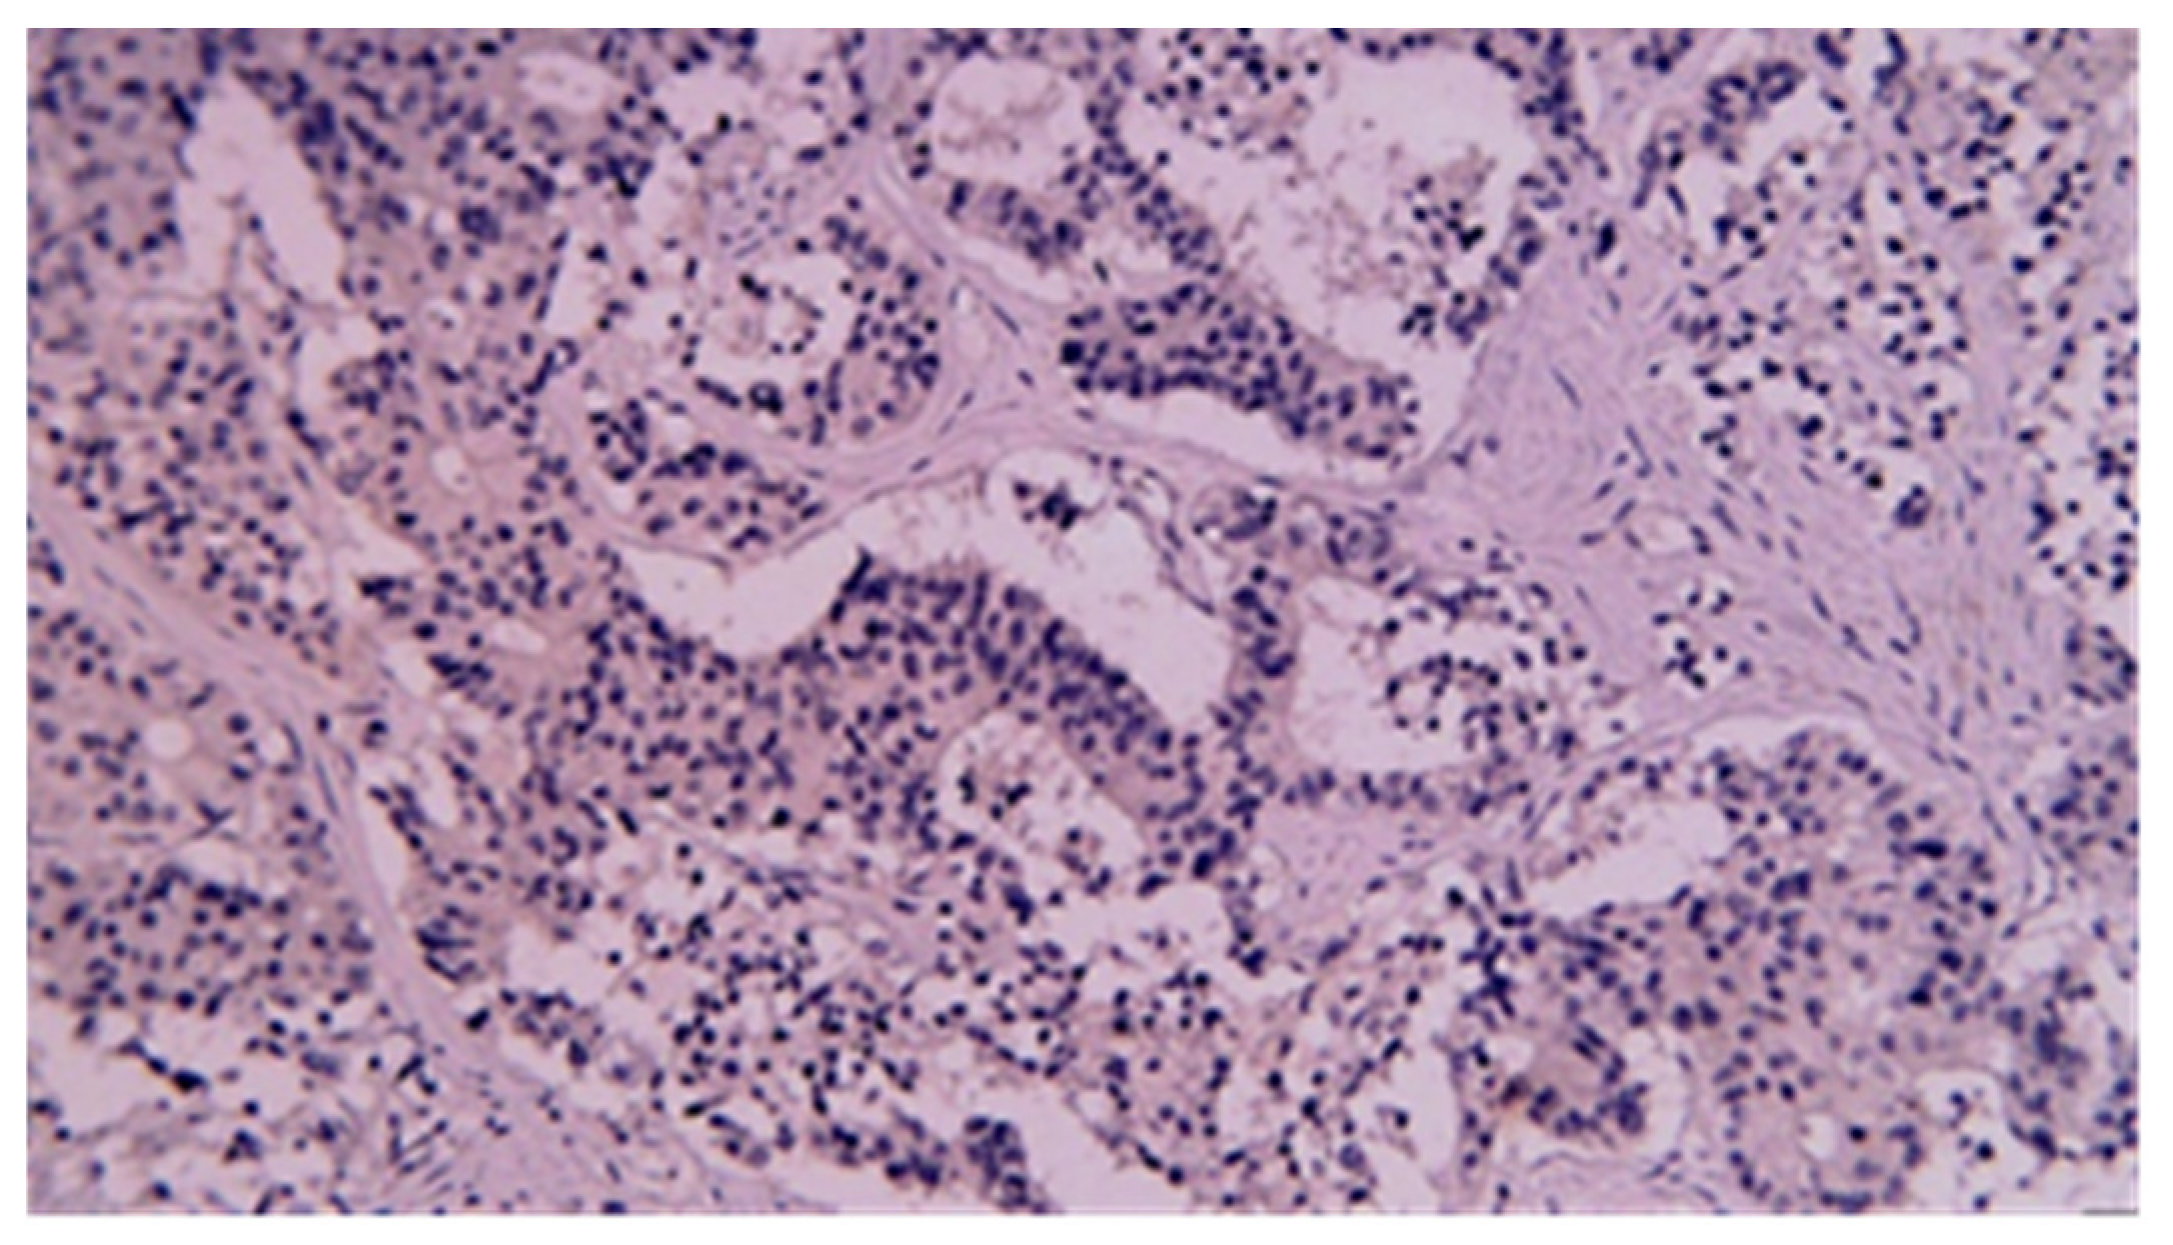

3.3. Immunohistochemistry

| Pathology No (%) | |

| Benign | 22 (27.5) |

| GIST | 8 (36.4) |

| Fibroid inflammatory | 6 (27.5) |

| Epithelial (adenoma, hyperplastic) | 5 (22.7) |

| Lipoma | 1 (4.5) |

| Hemangioma | 1 (4.5) |

| Hamartoma | 1 (4.5) |

| Malignant | 58 (72.5) |

| Primitive carcinoma | 28 (48.3) |

| Adenocarcinoma | 24 (41.4) |

| Squamous cell carcinoma (1 mixed) | 2 (3.4) |

| Undifferentiated carcinoma | 1 (1.7) |

| Carcinosarcoma | 1 (1.7) |

| Lymphoma | 8 (13.8) |

| NET | 6 (10.3) |

| GIST | 6 (10.3) |

| Metastasis | 6 (10.3) |

| Carcinoma (1 from squamous cell carcinoma) | 3 (5.2) |

| Melanoma | 3 (5.2) |